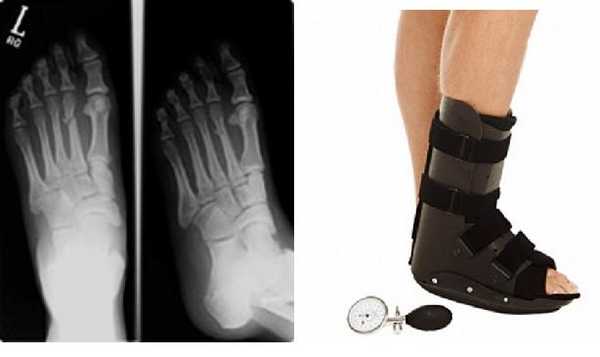

Как правило при травматических переломах рекомендуют ходить только с опорой на пятку либо вовсе без опоры, передвигаясь с костылями.

При стресс-переломах рекомендуется ходить с частичной нагрузкой на стопу, но обязательно в индивидуальных ортопедических стельках, которые «разгружают» поврежденный участок.

При изолированных переломах 2-3-4 плюсневых костей без смещения показано консервативное лечение в брейсе или короткой гипсовой повязке с постепенным увеличением нагрузки по мере регресса болевого синдрома.